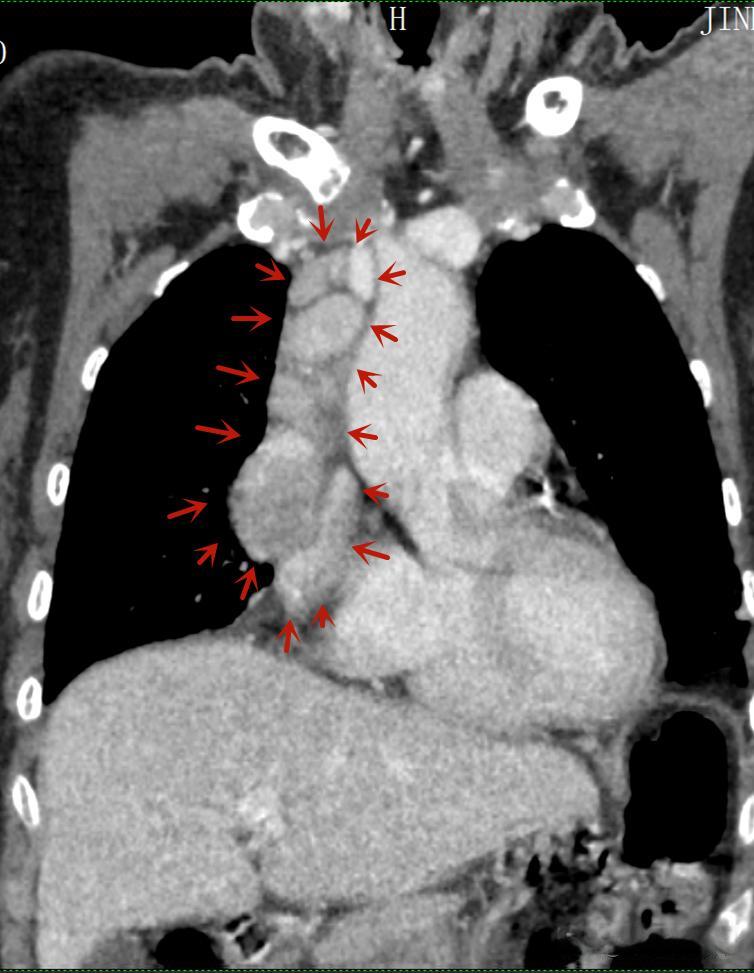

44岁的小敏因持续咳嗽一个月来到武汉协和医院就诊。经过CT检查,医生发现她患有前上纵隔肿瘤。这个发现让小敏既惊讶又担忧,因为她除了咳嗽外并没有其他明显症状。幸运的是,由于及时发现和治疗,小敏在协和医院专家的手术治疗下顺利康复出院。

诊断纵隔肿瘤通常需要进行一系列检查。胸部X线检查是初步筛查的重要手段,而CT和核磁共振(MRI)则能提供更详细的信息,帮助医生判断肿瘤的性质和与周围结构的关系。正电子发射计算机断层扫描(PET)在某些情况下也能提供有价值的诊断信息。